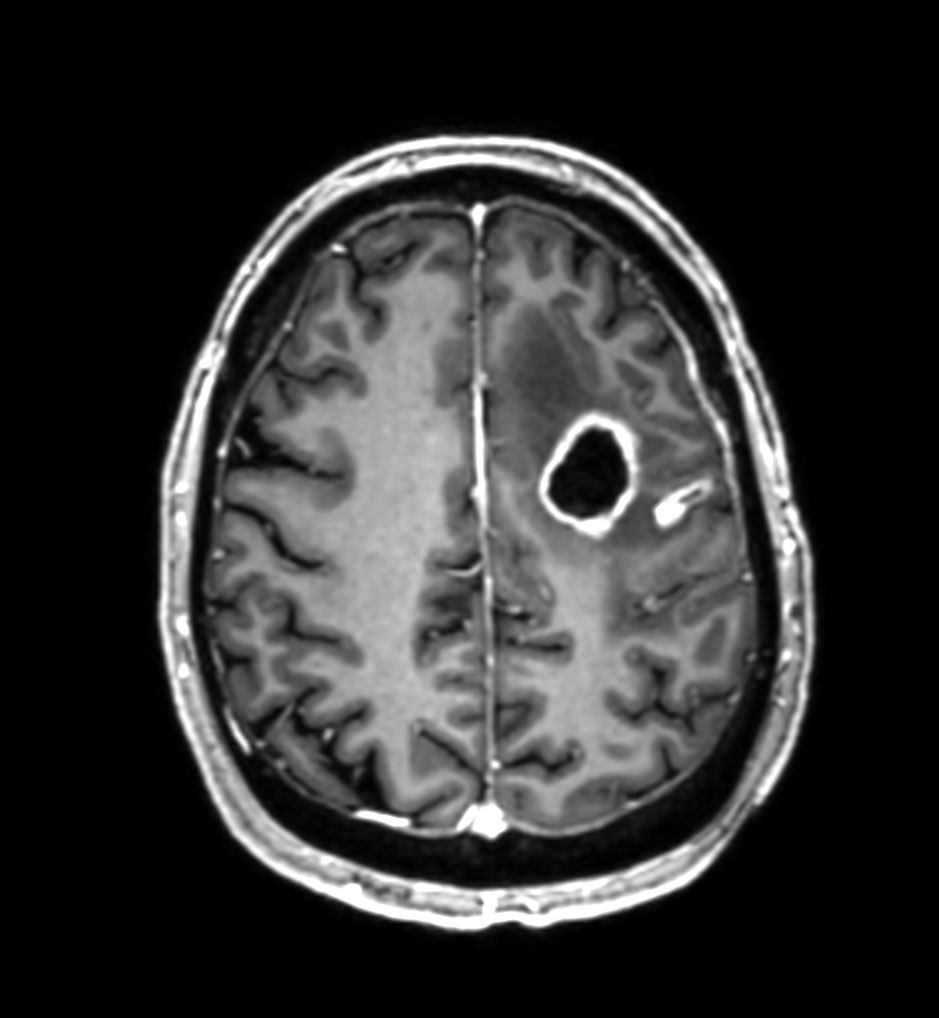

3D T1w TFE - Axial reformat